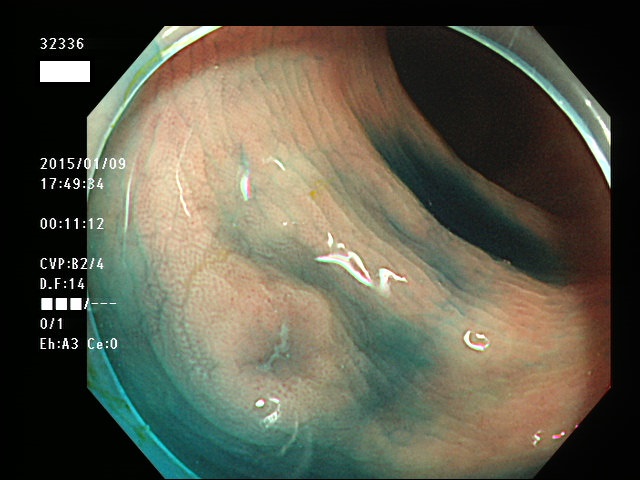

上記100名より抽出した平坦・陥凹型腺腫(=癌化の危険が高いが見落としやすい病変)の内視鏡写真